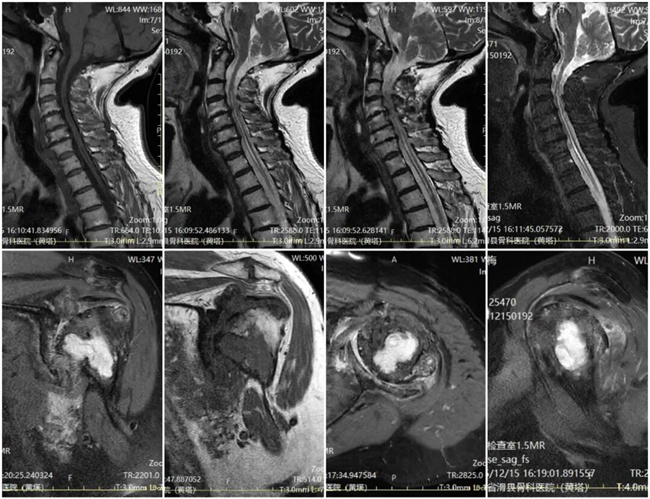

一、患者李某某,女,69岁,患者左上臂酸沉不适6年余,加重一天,左上臂酸沉麻木,感觉减退,活动受限。为求进一步治疗,来到我院请专家会诊,通过各位专家会诊查体、查看影像资料并细致认真的分析后,诊断为:脊髓空洞症,意见:保守治疗。

二、患者张某某,男,52岁,患者双下肢乏力2年余,腰部不适,双下肢无力,右上肢痛觉、温度觉减退,易摔倒活动受限。为求进一步治疗,来到我院请专家会诊,通过各位专家会诊查体、查看影像资料并细致认真的分析后,诊断为:脊髓空洞症,意见:进一步颈椎检查(神经外科治疗)。